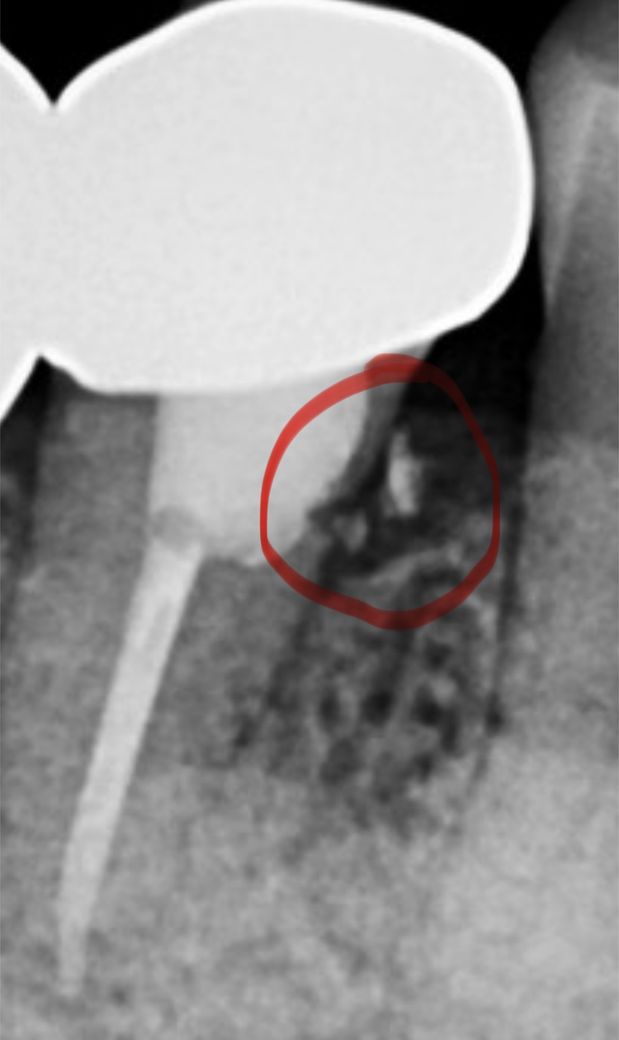

치아,이부분은 무엇인가요????

신경치료 전 후 사진인대요

뭔가 깨진거로 보이는데

크랙일까요???음영이나 잇몸인걸까요?

사진으로 정확히 알기는 힘듭니다. 다만 치아에서 떨어지는 것으로 보아 신경치료 과정에서 사용한 충전재 및 재료일 가능성이 있어 보입니다. 정확한 판단을 위해서는 해당 치과에 신경치료를 시술한 치과의사 선생님과 상담이 필요할 것으로 보여집니다.

크랙이나 음영보다는 이물질로 보이지만 엑스레이만으로 무엇인지는 알 수 없을 것 같습니다.

크랙간부분은 아니고 충치 잇는부분에 단단한 재료가 조금 덜 들어 간거 같습니다. 크라운 프랩할떄 마무리 해주실꺼에요.

신경 치료를 하는 도중에 신경관의 특정 부위에 구멍이 나게 되면 치과 재료로 해당 부위를 충전할 수 있는 경우가 있습니다.

해당 부위로 인해서 뜨거운 물에 자극이 발생하거나 하지는 않을 것으로 생각되나 자세한 확인을 위해서 치과에서 진료를 받아보는 것을 권유 드립니다.

신경치료 후 엑스레이 사진 상에서 보이기로는 부골이 아닐까 싶습니다. 특별히 증상이 없다면 그냥 정기적으로 체크하면서 관찰하면 됩니다.